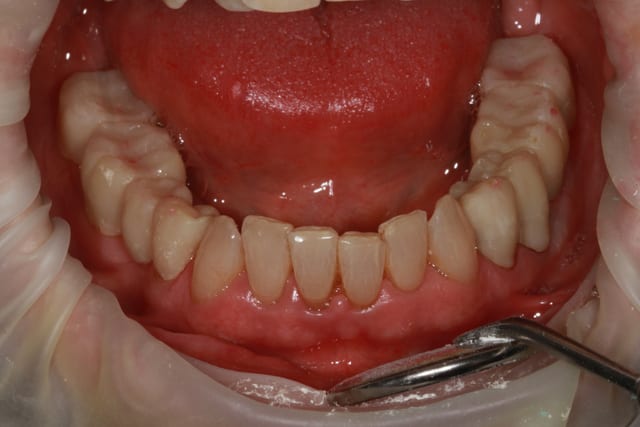

le problème de départ de cette patiente est paro...et bien sur l'ortho est une bonne idée, mais je ne pense pas que l'ortho permette de rétablir une DV correcte.

donc dans un premier temps détartrage, détartrage, détartrage Wax up, ....surfaçage couronne , amalgame à la benne taille des postérieurs inférieure et pose de provisoires pour valider la nouvelle DV.

Tout à fait d'accord avec le manque de calage par effondrement des spee. Il y a par contre égression du bloc incisif supérieur, d'où surcharge occlusal ne favorisant pas la paro, si on attend trop tout s'écroule. Une réingresser par de l'ortho sur un terrain paro fragile est super long, voir dangereux (aggravation de la paro), le choix de se passer d'ortho ici semble plutôt logique, il est urgent de régler l'occlusion et d’alléger le sur-guidage incisif (le rôle des provisoires molaire mandibulaire).

La ligne du sourire semble trop basse, et la ligne des collets est a remonter. Les couloirs vestibulaires sont sombre. Rajouter du volume en vestibulaire permettrait d'illuminer le sourire, donc facette Emax de 16 à 26 (peut être CCC en postérieur à la place des facettes, si on doit encore peaufiner l'occlusion). Globalement c'est peu ou pas mutilant car le manque est surtout vestibulaire.